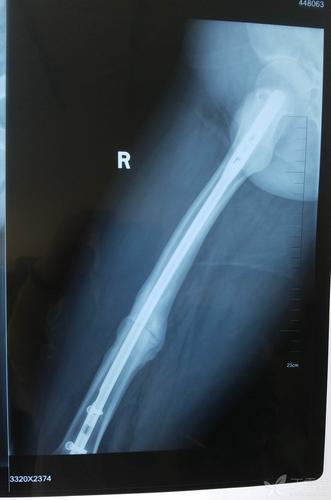

看这例股骨干骨折术后接下来将如何处理?

写美篇 第一例患者为42岁女性,体态偏胖,右股骨干中下段骨折,九个月前

股骨干骨折不愈合次置骨换钉十钢板固定

股骨干骨折髓内钉图片